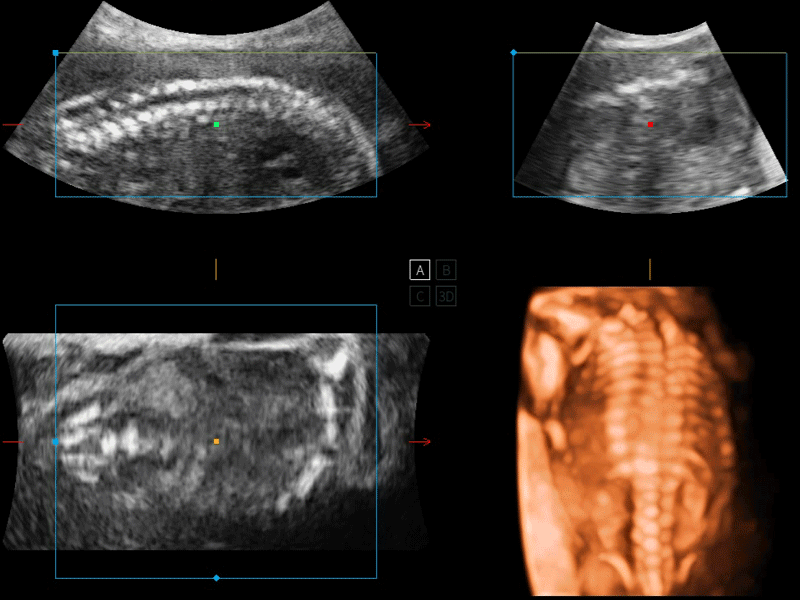

容积探头

凭借狗万官方网站先进的成像技术和优异的探头技术提供的清晰的图像表现,您可以更自信地做出临床决策。